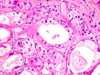

CASO N° 4 (Dr. Bonan e Dr. Roman)

Paciente do gênero masculino, 46 anos de idade, apresenta lesão no palato.